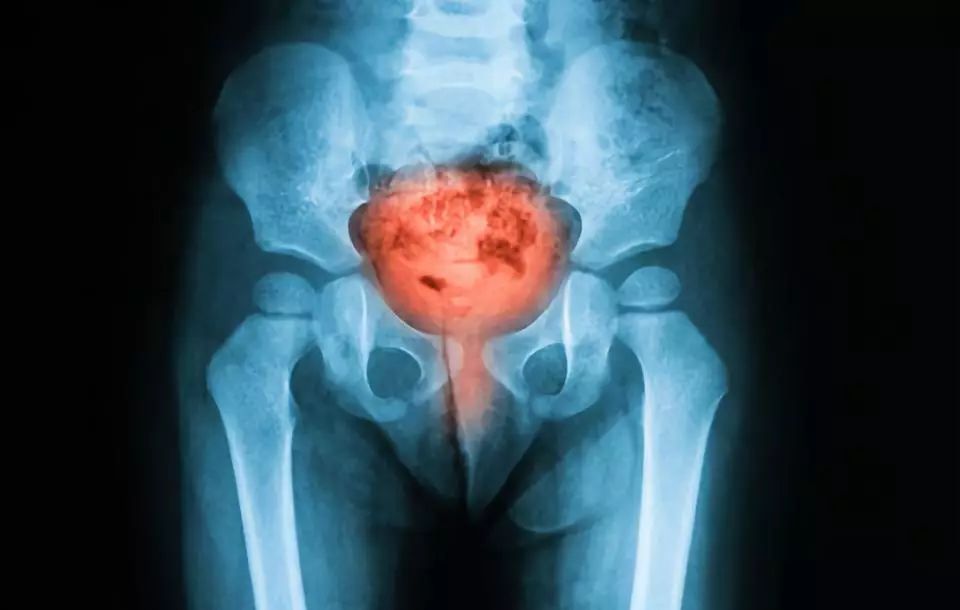

原因 7:膀胱感染

你可能认为男人不会得膀胱感染,因为膀胱感染的概率很小。虽然不太常见,但也有发生的可能。当他们患有前列腺肥大、肾结石或因性传播感染或受伤导致尿道狭窄时,膀胱有一定几率会受到感染。膀胱感染的症状包括灼烧或刺痛、发烧、尿带血或混浊。